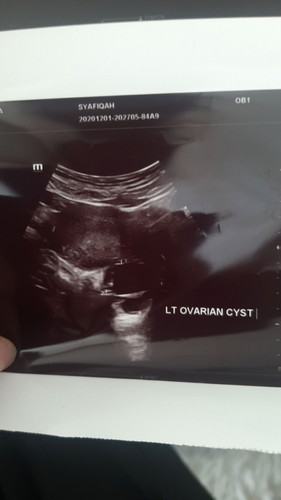

Kemunculan Cyst pada Minggu ke 5.

Semalam pergi scan.. cari kantung mula2 doc tak jumpe.. pusing2 jumpe cyst 😔 lepas jumpe cyst baru nampak kantung. Mood terus down. Siapa ade pengalaman begini? Apa yg perly saya atasi? #firstbaby #bantusharing #pregnancy #mommybuntu